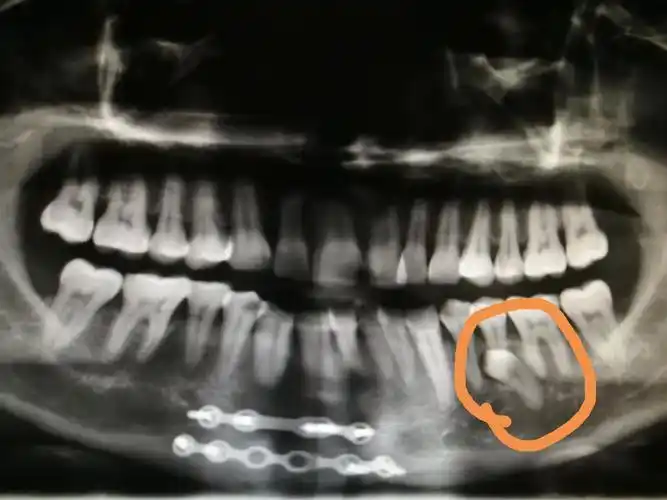

术后ct片,体会:牙齿缺失要及时修复喔!

做全景ct时,还能一并照到牙龈结构和骨龄,可谓是一举三得.

牙科ct有助于完全埋伏牙拔除术